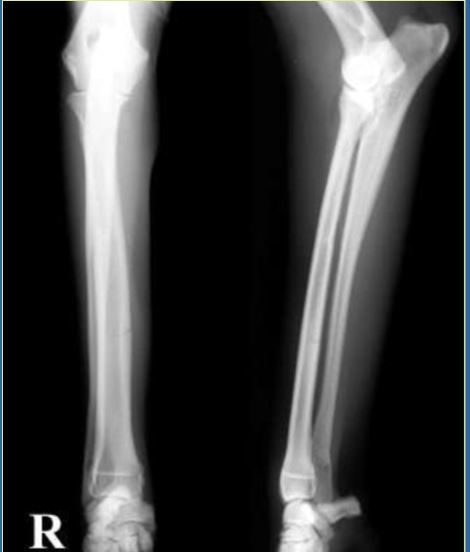

10

Q

4 year old F St.Bernard, 50kg

HBC 1 week ago

Classify and assess fracture, and give repair options

A

Transverse fractures of the radius and ulna

Fx score= 5

Repair: 2 plates- one on radius and one on ulna (because of size, if had been smaller would not need ulnar plate)